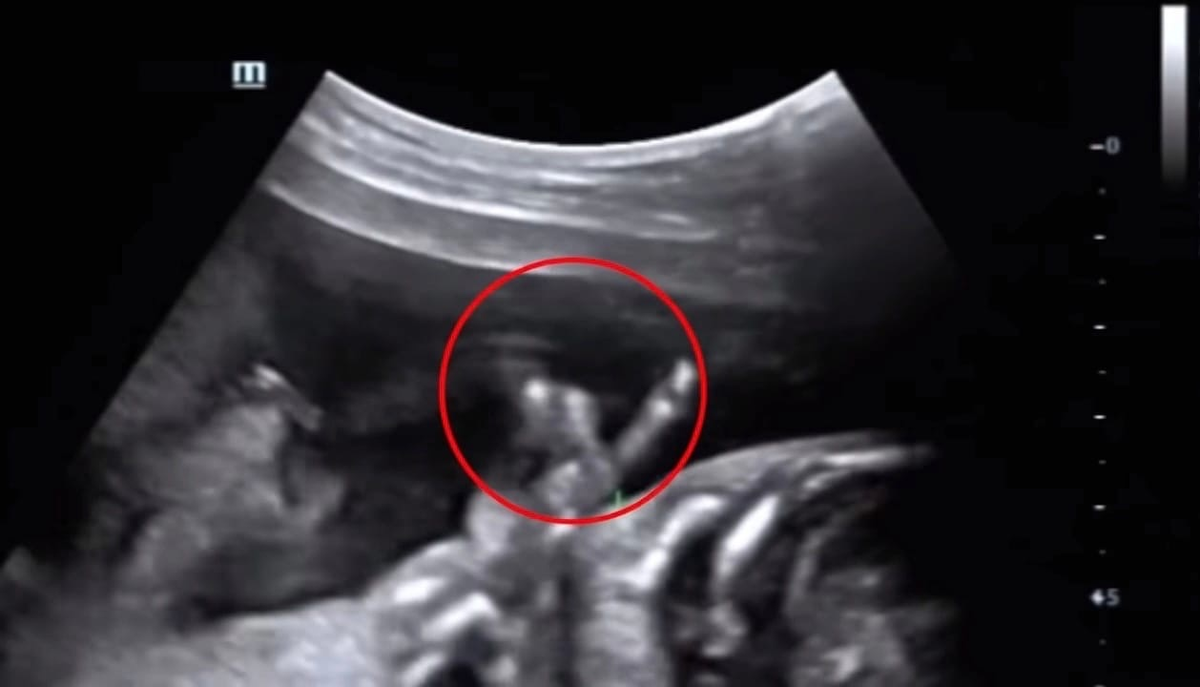

Ребенок исчез во время узи как называется